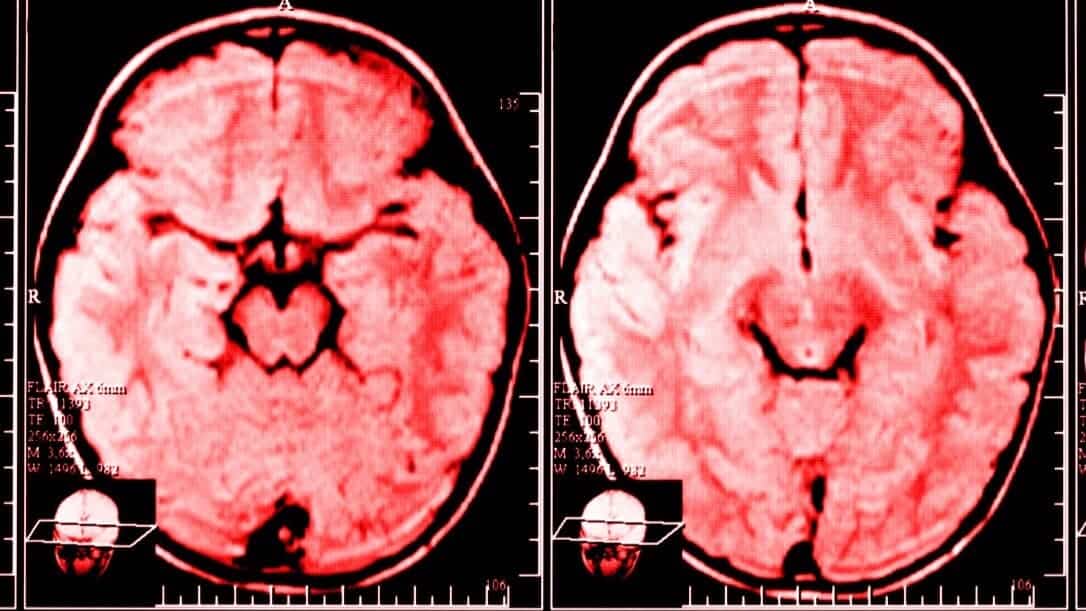

Nos últimos 20 anos, graças ao rápido desenvolvimento nas esferas da imagem cerebral e da neurociência, podemos agora dizer com certeza que o cérebro é capaz de fazer reengenharia em si mesmo.

De muitas maneiras, a ‘neuroplasticidade’ – um termo genérico que descreve a mudança duradoura no cérebro ao longo da vida de uma pessoa – é uma área fascinante da ciência.